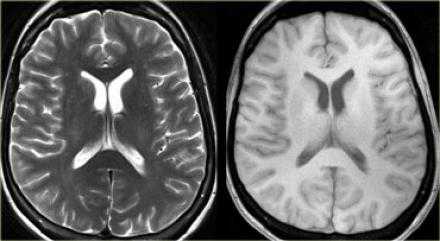

Т2-взвешенные изображения

Высокая интенсивность сигнала на Т2-ВИ не проявляется в первые 8 часов после начала ишемического инсульта. Гиперинтенсивность характерна для хронической фазы, достигая максимума в подострый период. Феномен затуманивания на МРТ может визуализироваться спустя 1-4 недели после инсульта с пиком, приходящимся на 2-3 неделю, он проявляется как изоинтенсивная относительно ГМ область, которая, как считается, является следствием инфильтрации зоны инфаркта воспалительными клетками. При обширных поражениях может происходить утрата нормального потока сонной артерий с ипсилатеральной стороны на Т2-ВИ спустя 2 часа после возникновения симптомов.

На PD/T2WI и FLAIR выглядит гиперинтенсивно. На PD/T2WI и FLAIR последовательностях возможно диагностировать до 80% инфарктов впервые 24 часа, но впервые 2-4 часа после инсульта изображение также может быть неоднозначным. На PD/T2WI и FLAIR продемонстрировано гиперинтенсивность в районе левой средней мозговой артерии. Обратите внимание на вовлечение в процесс лентиформного ядра и островковой доли. Область с гиперинтенсивным сигналом на PD/T2WI и FLAIR соответствует гиподенсивной области на КТ, что в свою очередь прямой признак гибели клеток мозга.